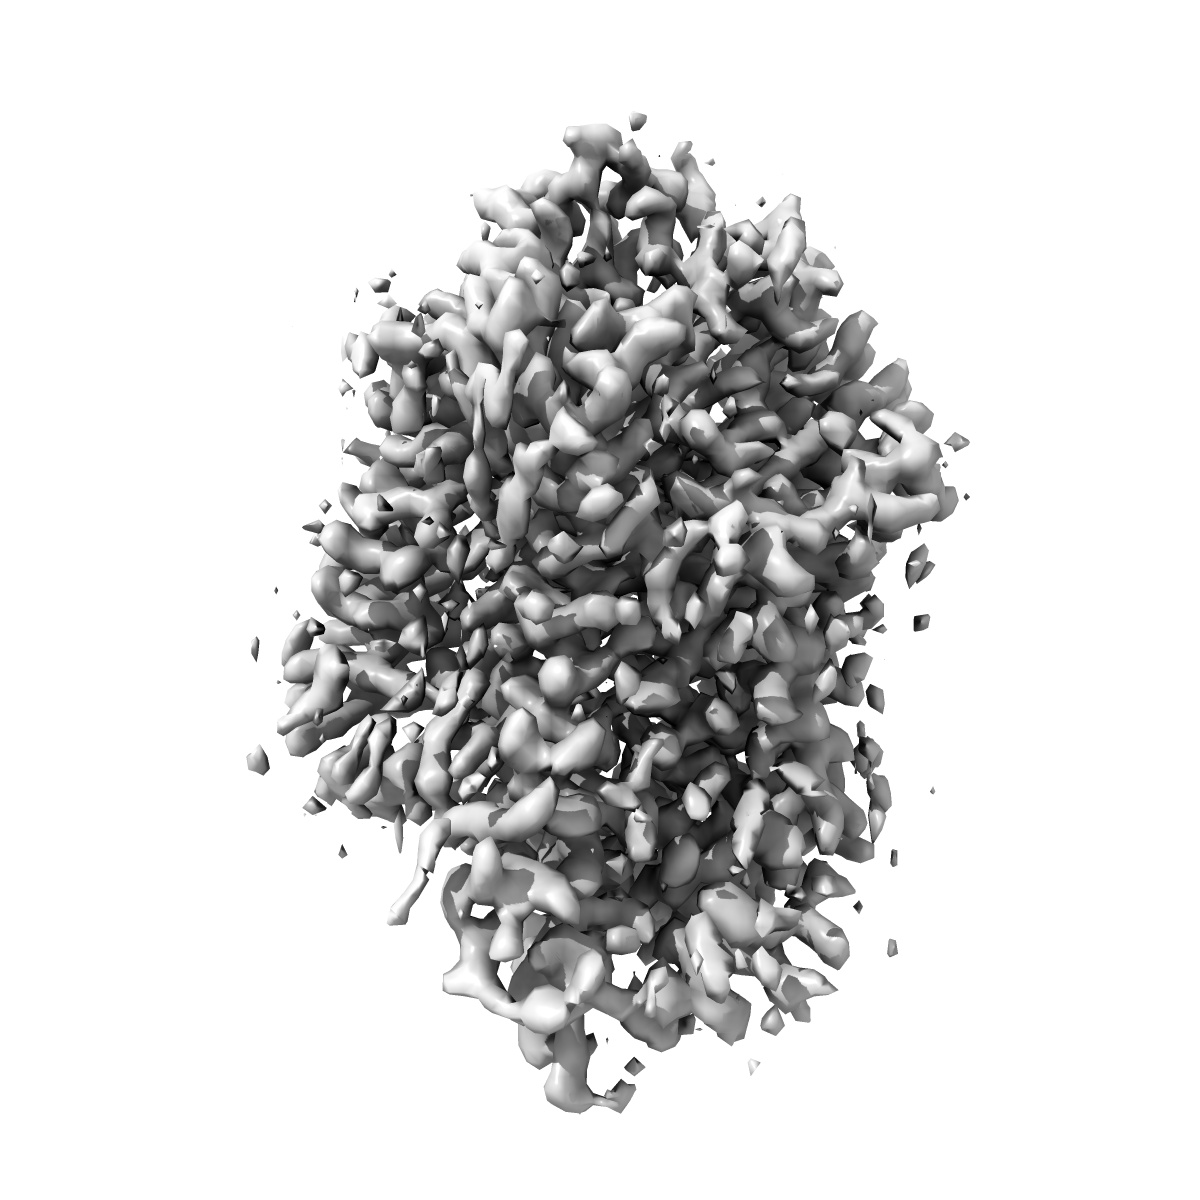

Cryo-EM structure of human norepinephrine transporter NET in the presence of dopamine in an inward-open state at resolution of 3.0 angstrom.

Single-particle3.0 Å

Fitted models: 8hfg

Molecular basis of human noradrenaline transporter reuptake and inhibition.

(2024) Nature , 632 , 921 - 929